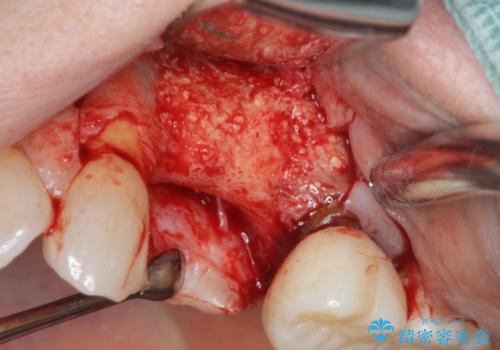

歯の穿孔(内部穴が開いている状態)破折等、歯を保存することができない問題が小臼歯には認められたので抜去を行います。

抜去後の補綴治療は長いブリッジではなくインプラント治療を希望されましたが、穿孔・破折による周囲の骨吸収をリカバリーすべく骨の造成を伴うインプラント治療を計画します。